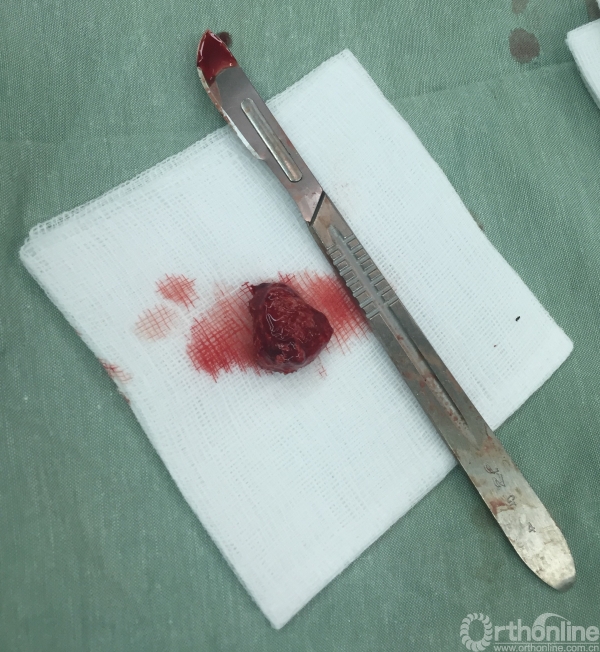

常年喝这样的水带来的结果就是很多人都有泌尿系结石,包括我们医疗队员也有。

这是一个12岁的男孩,在他的左肾里取出了一个直径1.5cm的结石。

是不是比三聚氰胺都厉害?